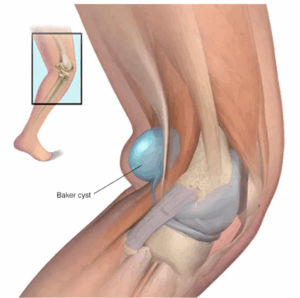

Baker cyst

A Baker cyst is a fluid-filled growth behind the knee. It causes a bulge and a feeling of tightness. Also called a popliteal (pop-luh-TEE-ul) cyst, a Baker cyst sometime causes pain. The pain can get worse when with activity or when fully straightening or bending the knee.